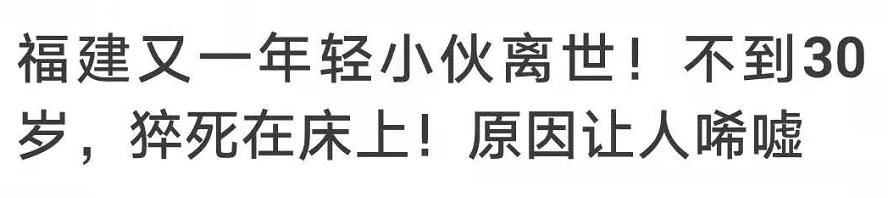

前几天,一条新闻震惊了我:

前几天,一条新闻震惊了我:

(新闻来源:泉州广播电视报)

(新闻来源:泉州广播电视报)“猝死”来得这么毫无征兆?

而让我更震惊的是:

根据他爸妈描述,小伙昨晚还像往常一样入睡,隔着房门都能听到他睡熟的鼾声。

直到第二天快中午,他还是没起。家人推门进去才发现,他早没有了呼吸心跳。

医生诊断,他是死于“睡眠呼吸暂停综合症”。简单的说,自己把自己憋死了。

医生诊断,他是死于“睡眠呼吸暂停综合症”。简单的说,自己把自己憋死了。 我查了一下这种病,结果发现,引起它的原因竟然是一件我们可能都做过的事:——打呼。